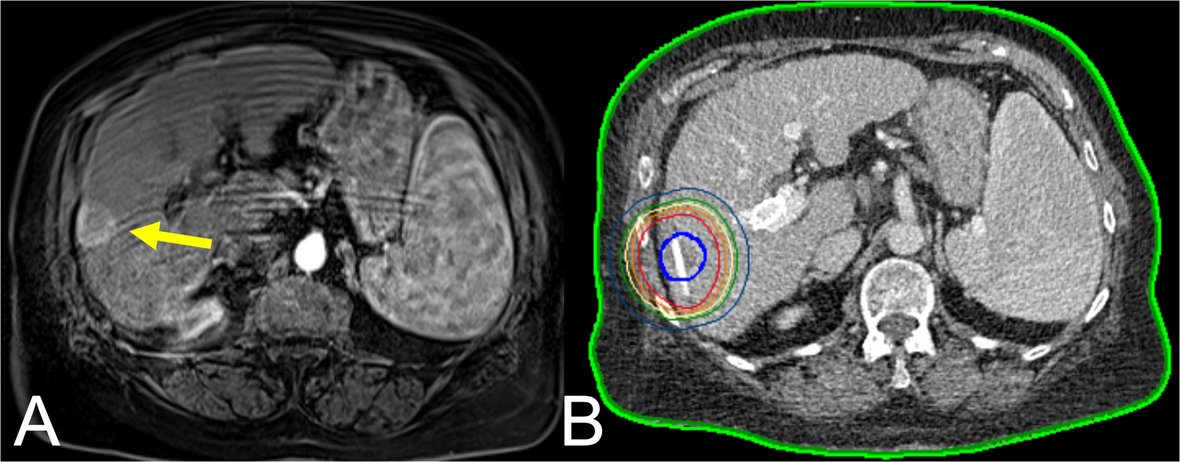

Read our recently published article on the effects of measurement errors on minimum ablative margins after thermal ablation of liver tumors: a simulation study

link.springer.com/article/10.100…